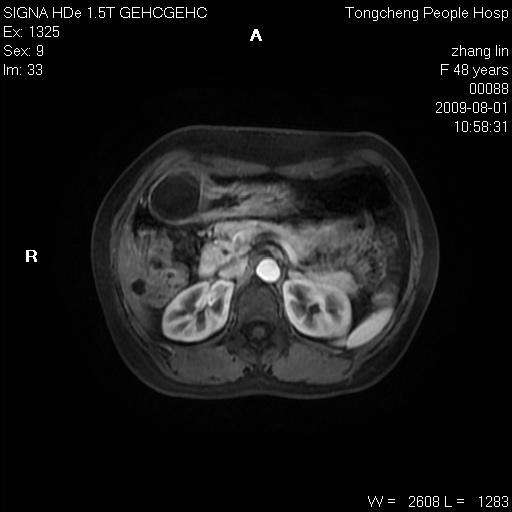

女,48岁。健康体检,彩超发现右肾占位性病变。平素健康。

临床诊断:右肾占位性病变,性质待定(囊肿?肿瘤?)。

上中腹部mr平扫+增强扫描,图像如下:

右肾上极见一类圆形病灶,t1wi呈等信号t2wi呈等高混杂信号,三期增强无强化,边界清---考虑囊肿出血。

同反相位均表现为等信号,病变无强化,考虑含蛋白的囊肿可能,弥散加权相或许有些帮助,